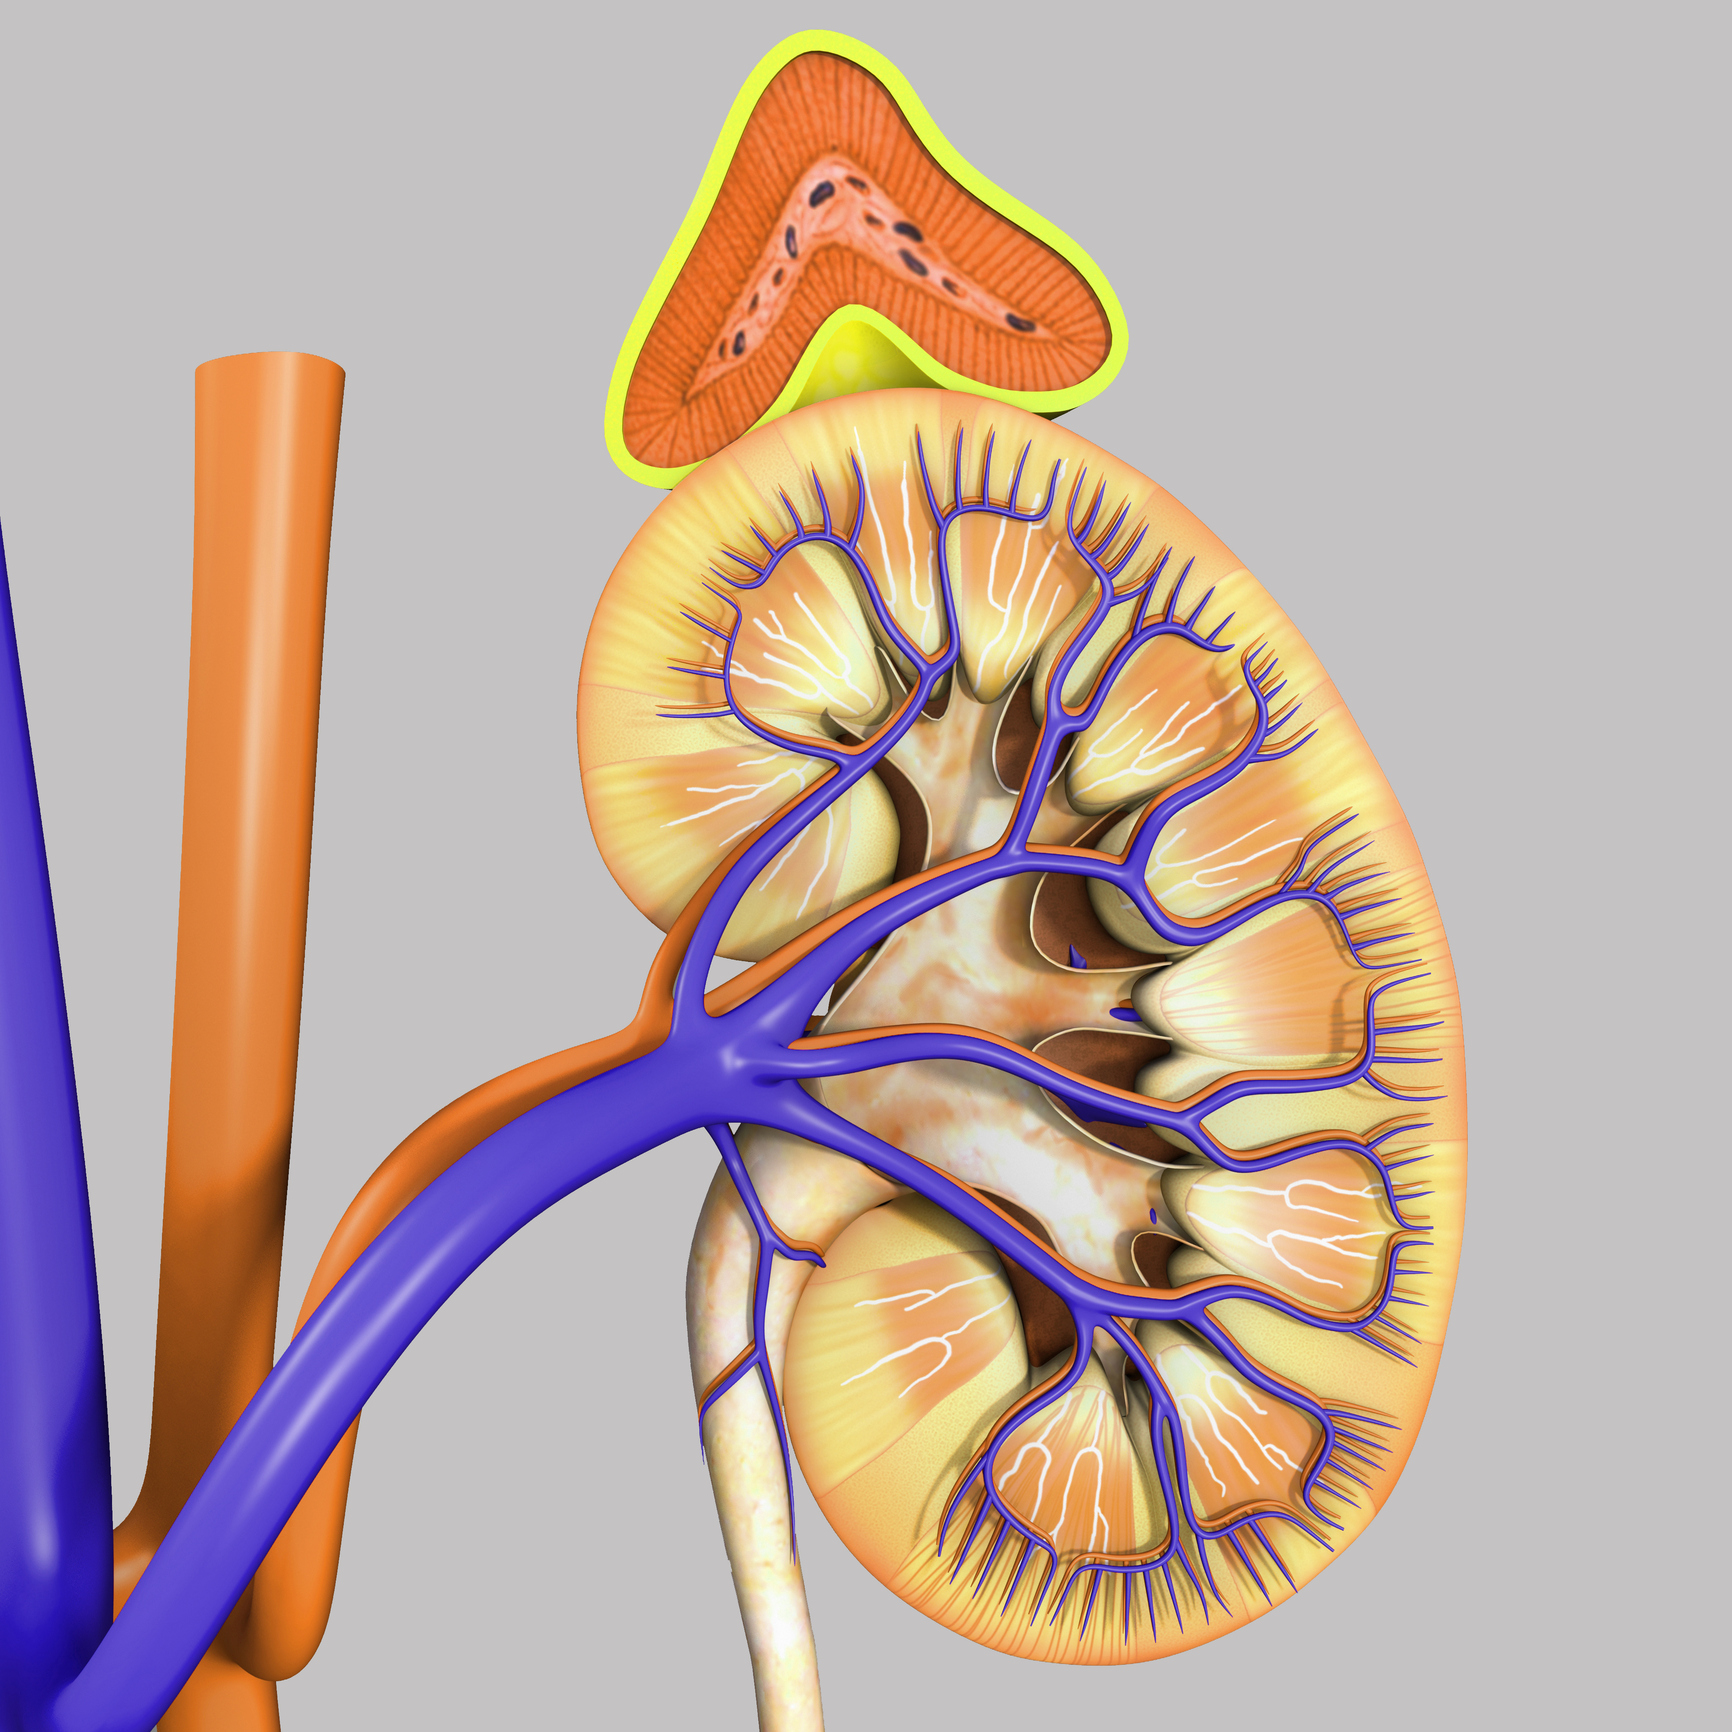

There are many factors that can contribute to high blood pressure such as being overweight, poor diet, and lack of physical activity. But there is another condition that can also lead to high blood pressure: it’s primary aldosteronism. Primary aldosteronism is a hormone disorder that can contribute to high blood pressure. Our adrenal glands are responsible ...click here to read more